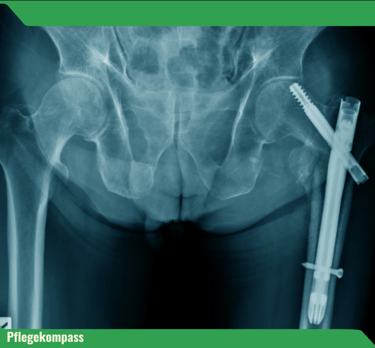

Ein Sturz bedeutet weit mehr als nur ein Ausrutschen – die Folgen reichen von Knochenbrüchen bis zum Verlust der Selbstständigkeit. Besonders häufig betroffen: der Oberschenkelhalsbruch. Über 90 % dieser Brüche entstehen durch Stürze.

Nur 40–60 % der Betroffenen mit Hüftfraktur erreichen ihre vorherige Mobilität wieder.

Menschen mit Pflegebedarf haben ein zehnfach höheres Risiko für Hüftfrakturen als Gleichaltrige ohne Pflegebedarf.